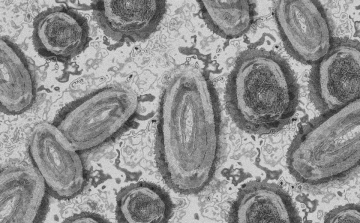

Tovább nőtt a majomhimlő-fertőzöttek száma Magyarországon

Újabb két embernél igazolt majomhimlő-fertőzést a Nemzeti Népegészségügyi Központ (NNK) a 33. héten - augusztus 15-től 21-ig -, ezzel 64-re nőtt a magyarországi esetek száma.

Meghaladta a 13 ezret a majomhimlő-fertőzöttek száma az Egyesült Államokban, a legtöbb esetet Kaliforniában és New York államban regisztrálták.

Megfertőződött a majomhimlővel egy gyerek Németországban

Megfertőződött majomhimlővel egy négyéves kislány Németországban - jelentették kedden német hírportálok az országos közegészségügyi intézet (RKI) adatai alapján.

Tovább nőtt a majomhimlő-fertőzöttek száma Magyarországon

Újabb kilenc, 23-50 éves férfinél igazolták a majomhimlő-fertőzést Magyarországon, ezzel 42-re nőtt a fertőzöttek száma - közölte a Nemzeti Népegészségügyi Központ (NNK) csütörtökön az MTI-vel.

Tovább nőtt a majomhimlő magyar fertőzöttjeinek száma

Újabb hat embernél diagnosztizálták a majomhimlő vírusát, így harmincra emelkedett az igazolt fertőzöttek száma Magyarországon - közölte a Nemzeti Népegészségügyi Központ (NNK) pénteken az MTI-vel.